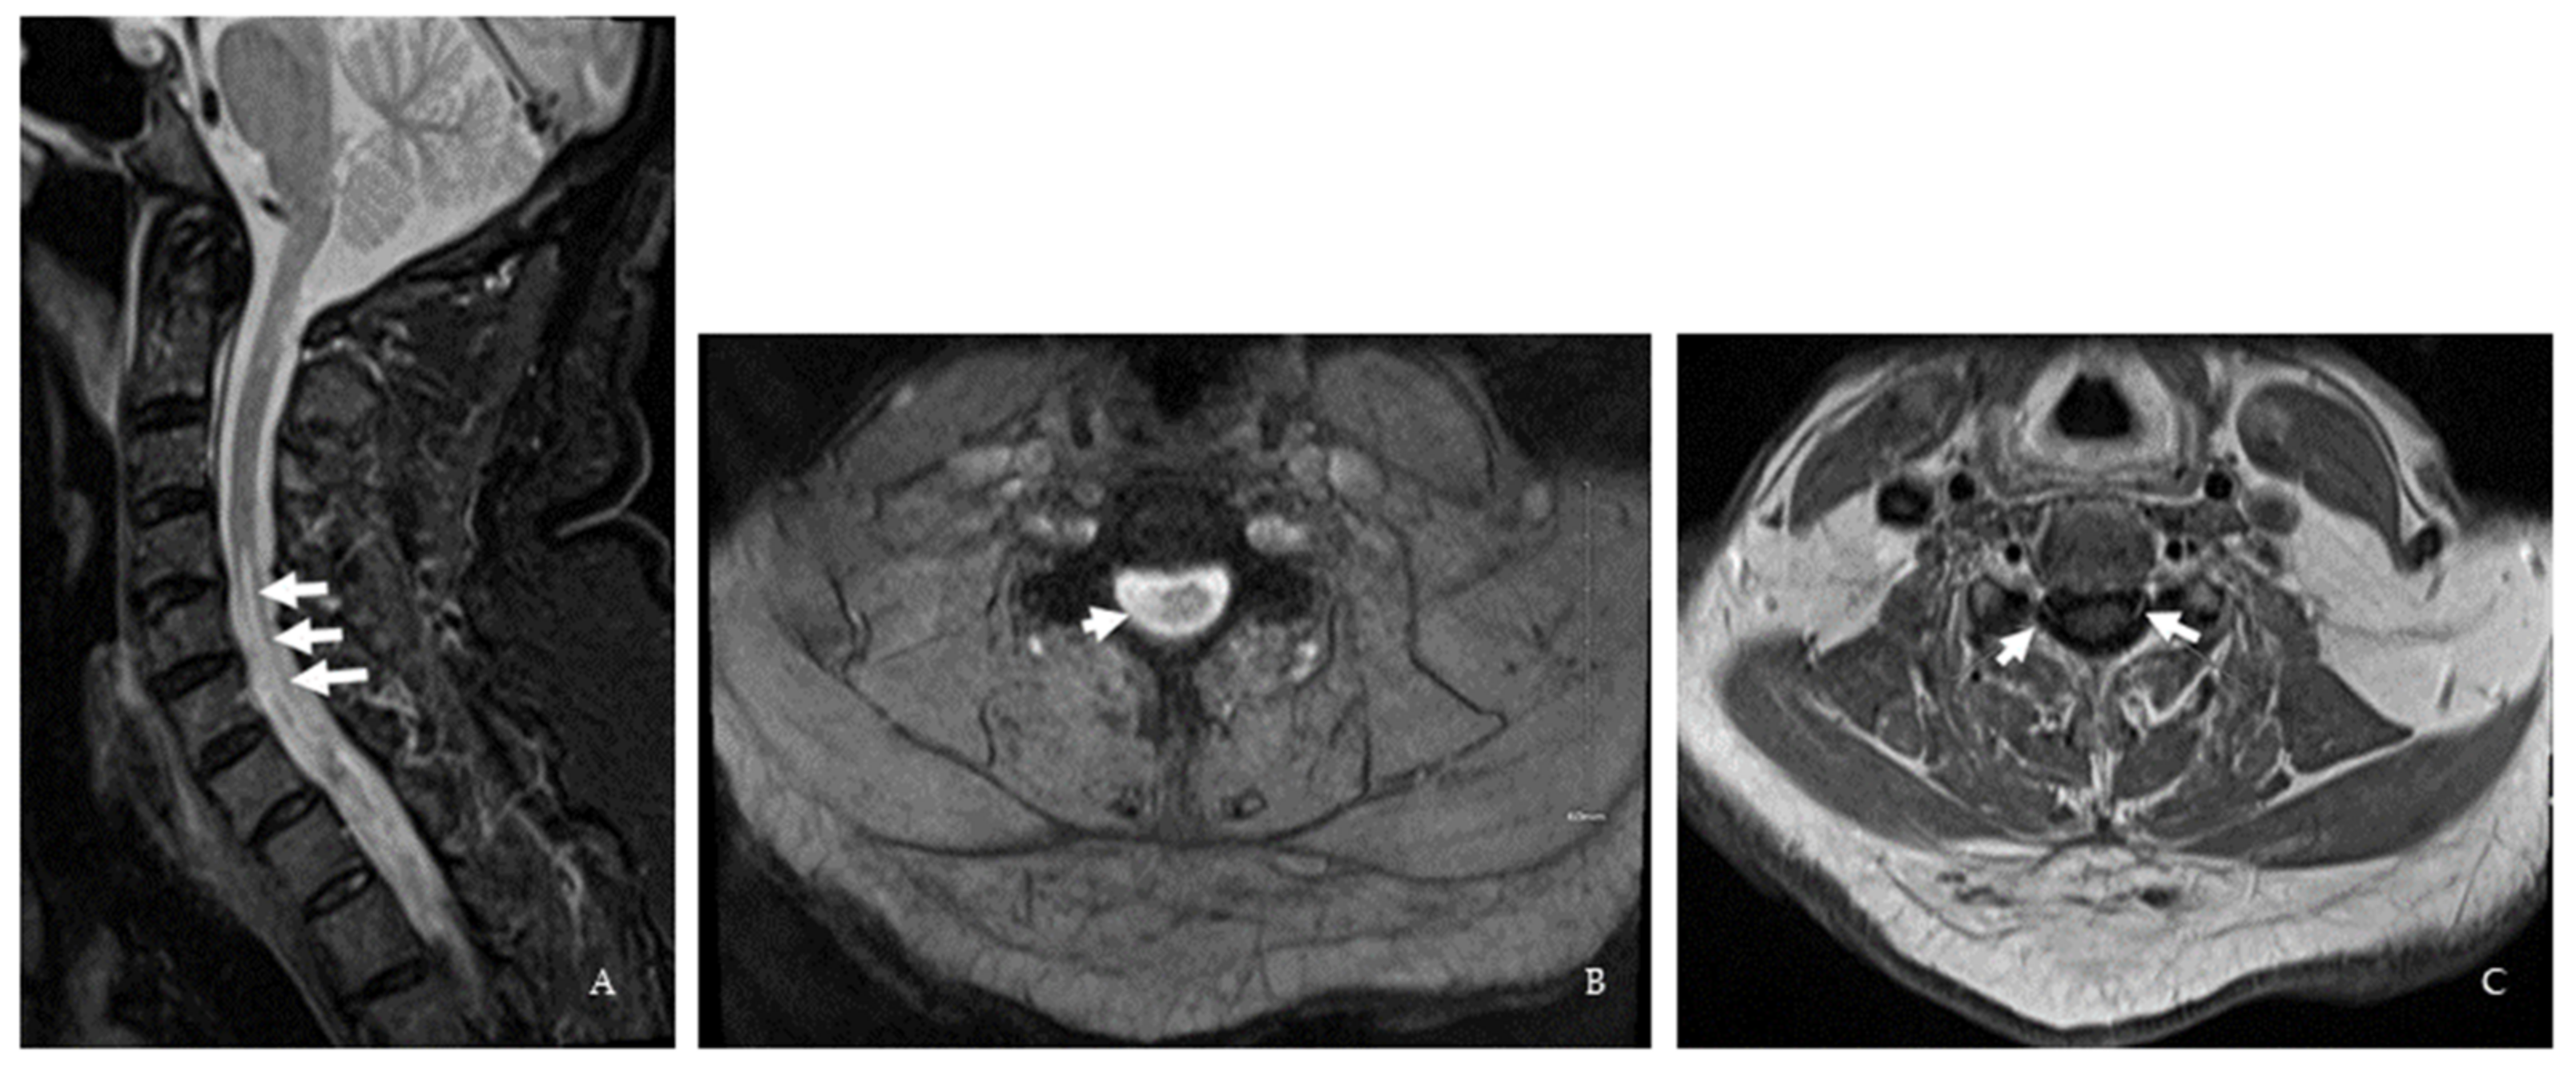

| Brain MRI | 1st event: Nonspecific multifocal T2/ FLAIR WML 2nd event: Nonspecific multifocal T2/ FLAIR WML | Periventricular and juxtacortical lesion, dorsal medullary lesion extending to cervicomedullary junction | Multifocal T2/ FLAIR WML | 1st MRI: Subcortical, periventricular, anterior temporal lobe, medullary lesions 2nd MRI: Stable | Periventricular, anterior cervico- medullary junction lesion | Periventricular and R frontal deep white matter lesions |

| Spinal cord MRI | 1st event: Cervical spine degenerative joint Disease 2nd event: C2-5 dorsal column T2 hyperintensity | C2-3 and T4 T2/ FLAIR lesions | ND | 1st MRI: C3, C5-6, C7-T1, and T8-9 lesions 2nd MRI: New C3 Gd-enhancing lesion | C2, C4-C7 lesion and cervical nerve root enhancement in the central cervical canal | 1st MRI: Age-related L4-5 changes 2nd MRI: C1 contrast-enhancing lesion 3rd MRI: C2 and C5 lesions |